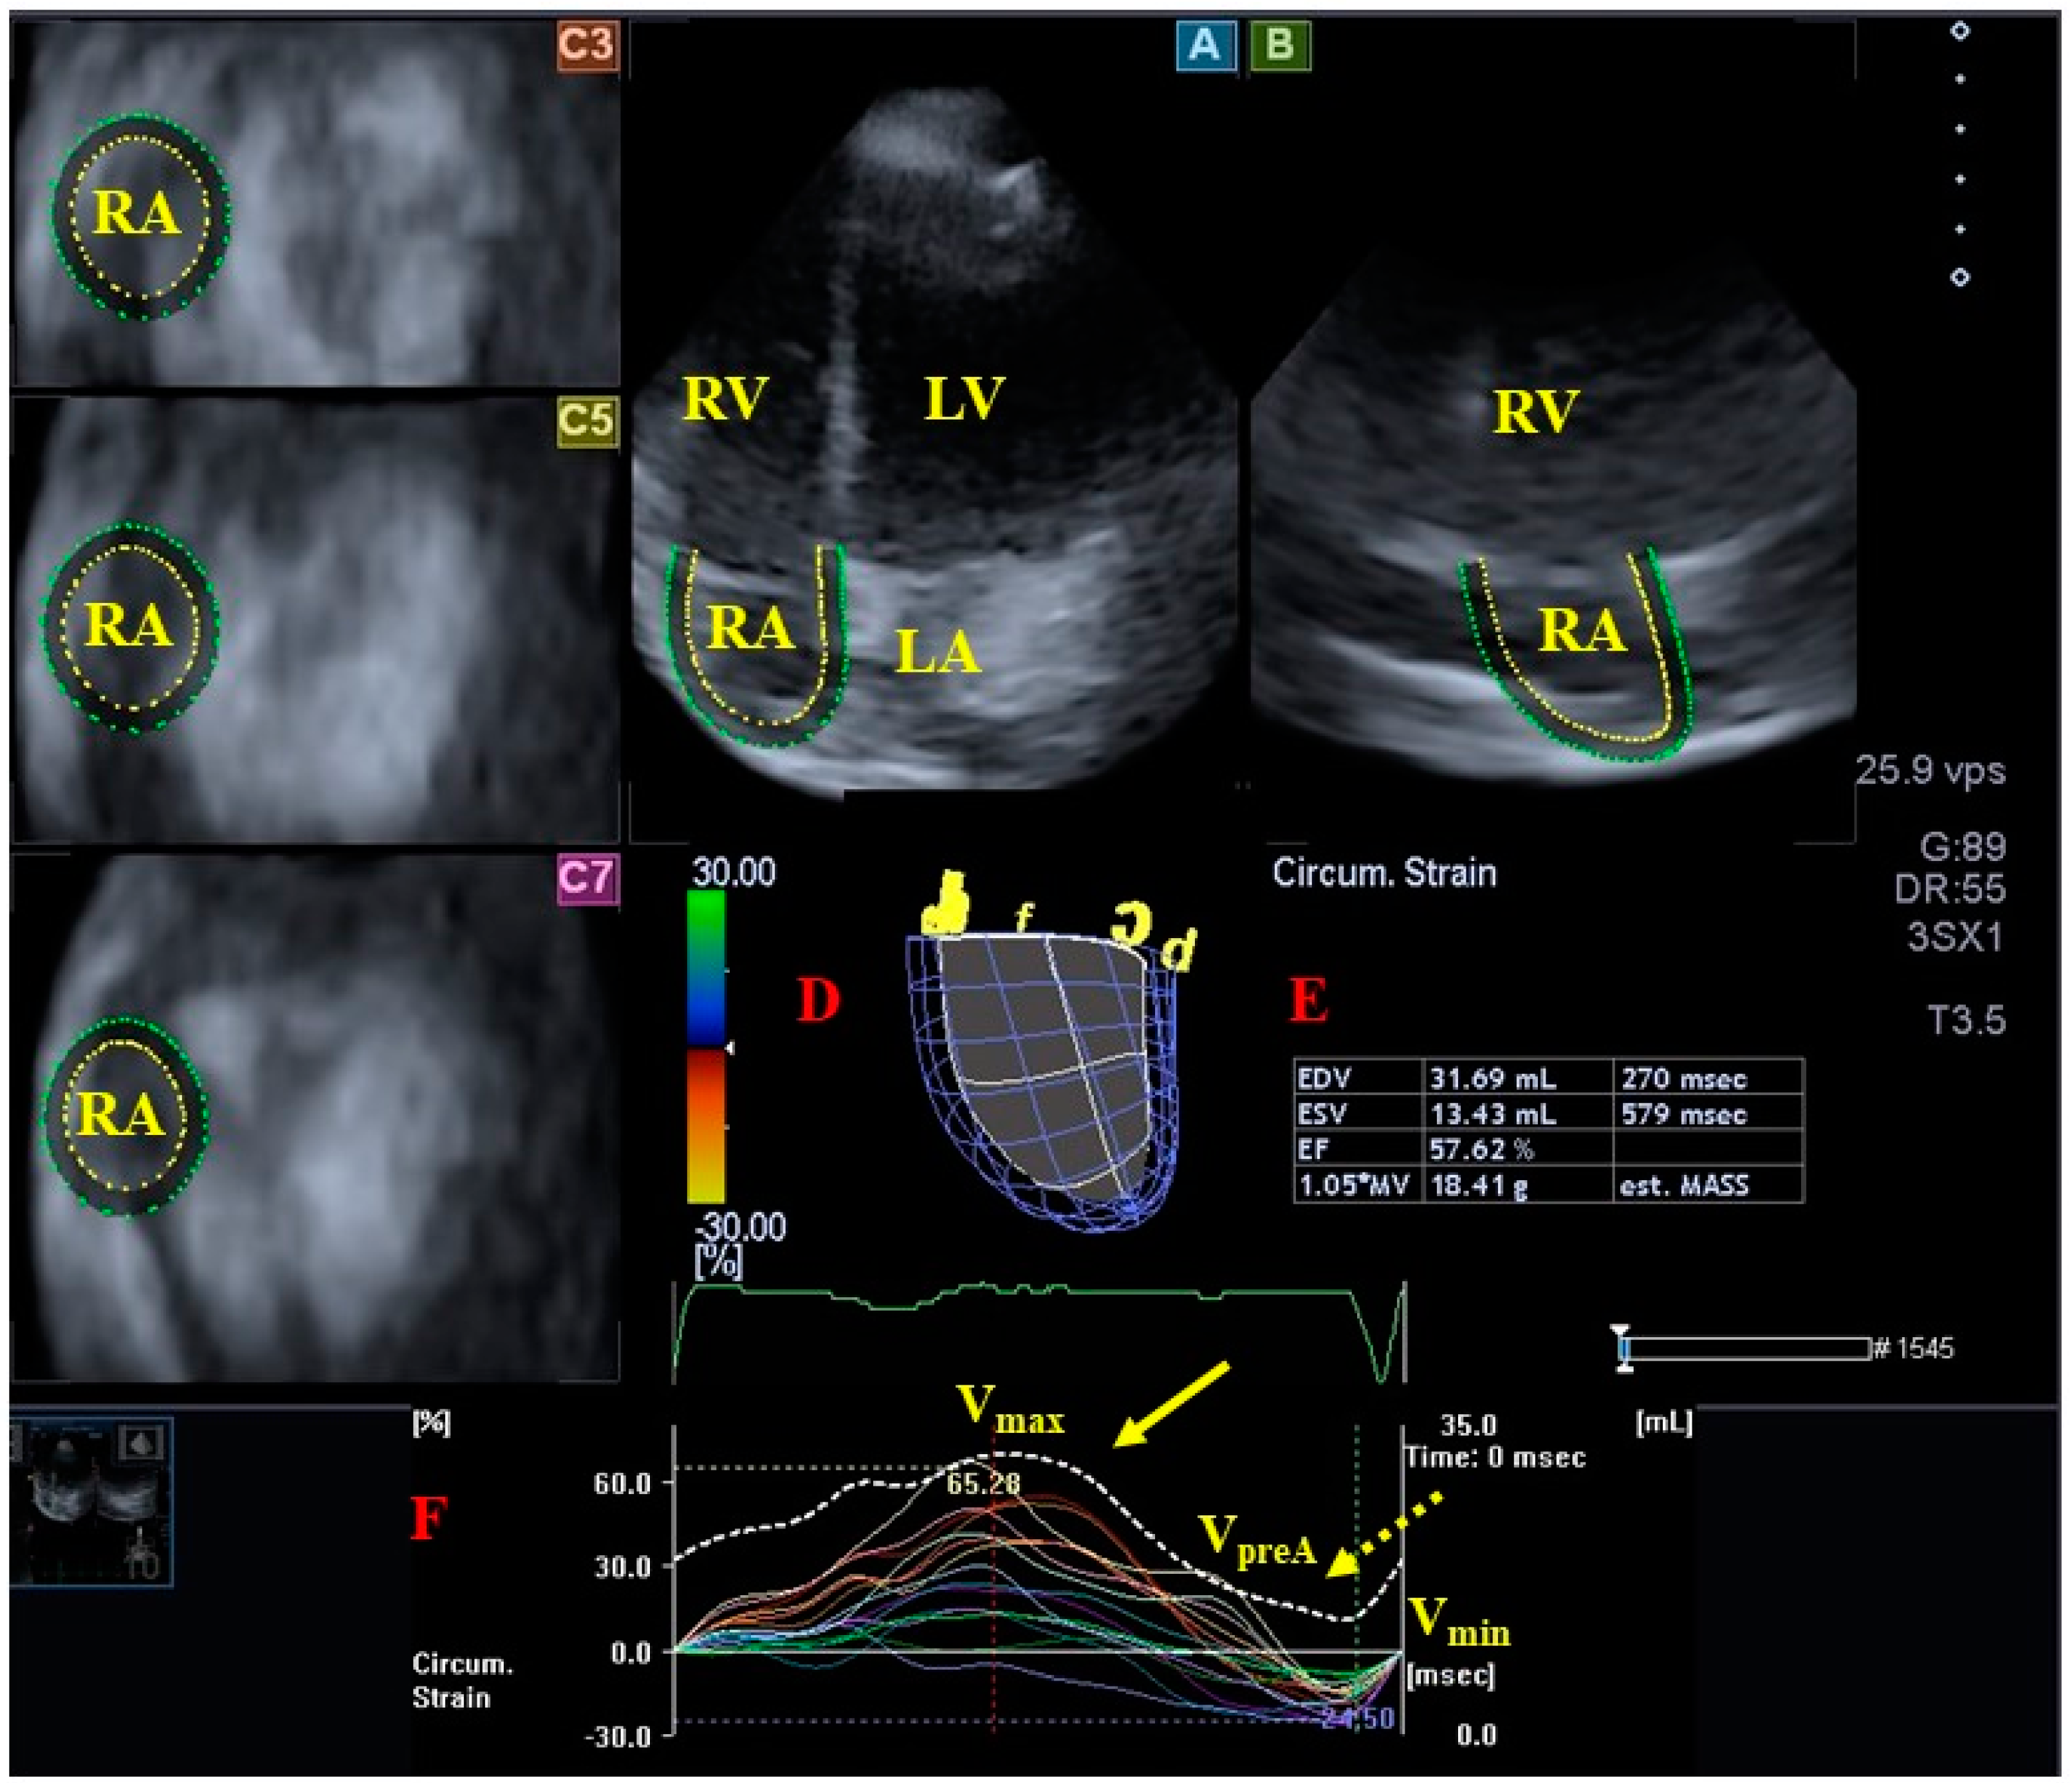

- Nemes, A.; Földeák, D.; Domsik, P.; Kalapos, A.; Kormányos, Á.; Borbényi, Z.; Forster, T. Right Atrial Deformation Analysis in Cardiac Amyloidosis—Results from the Three-Dimensional Speckle-Tracking Echocardiographic MAGYAR-Path Study. Arq. Bras. Cardiol. 2018, 111, 384–391. [Google Scholar] [CrossRef]